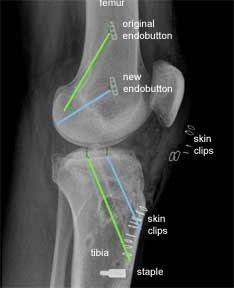

This is an X-ray, of the same patient, taken from the side instead of the front. The green lines show the original tunnels and the blue lines the new tunnels.

For the femoral tunnels the higher endobutton is from the original procedure and the lower endobutton is from the revision procedure.

The new tibial tunnel (blue) is more anterior (closer to the front) than the original tunnel. This is a more anatomic position for the tibial insertion of the native ACL.

To further help you to appreciate the differences between the two procedures, I have used a software programme to 'bend' the knee in the X-ray. This shows that the older trans-tibial procedure leads to parallel femoral and tibial tunnels. This is in contrast to the angled tunnels achieved using the ‘more anatomic’ approach.